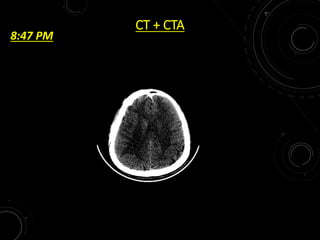

CT + CTA

8:47 PM

PATIENT - 8JULY • 35/M C/O SUDDEN ONSET WEAKNESS OF LEFT UPPER AND LOWER LIMB • TIME – SINCE 6 PM ON 8 JULY